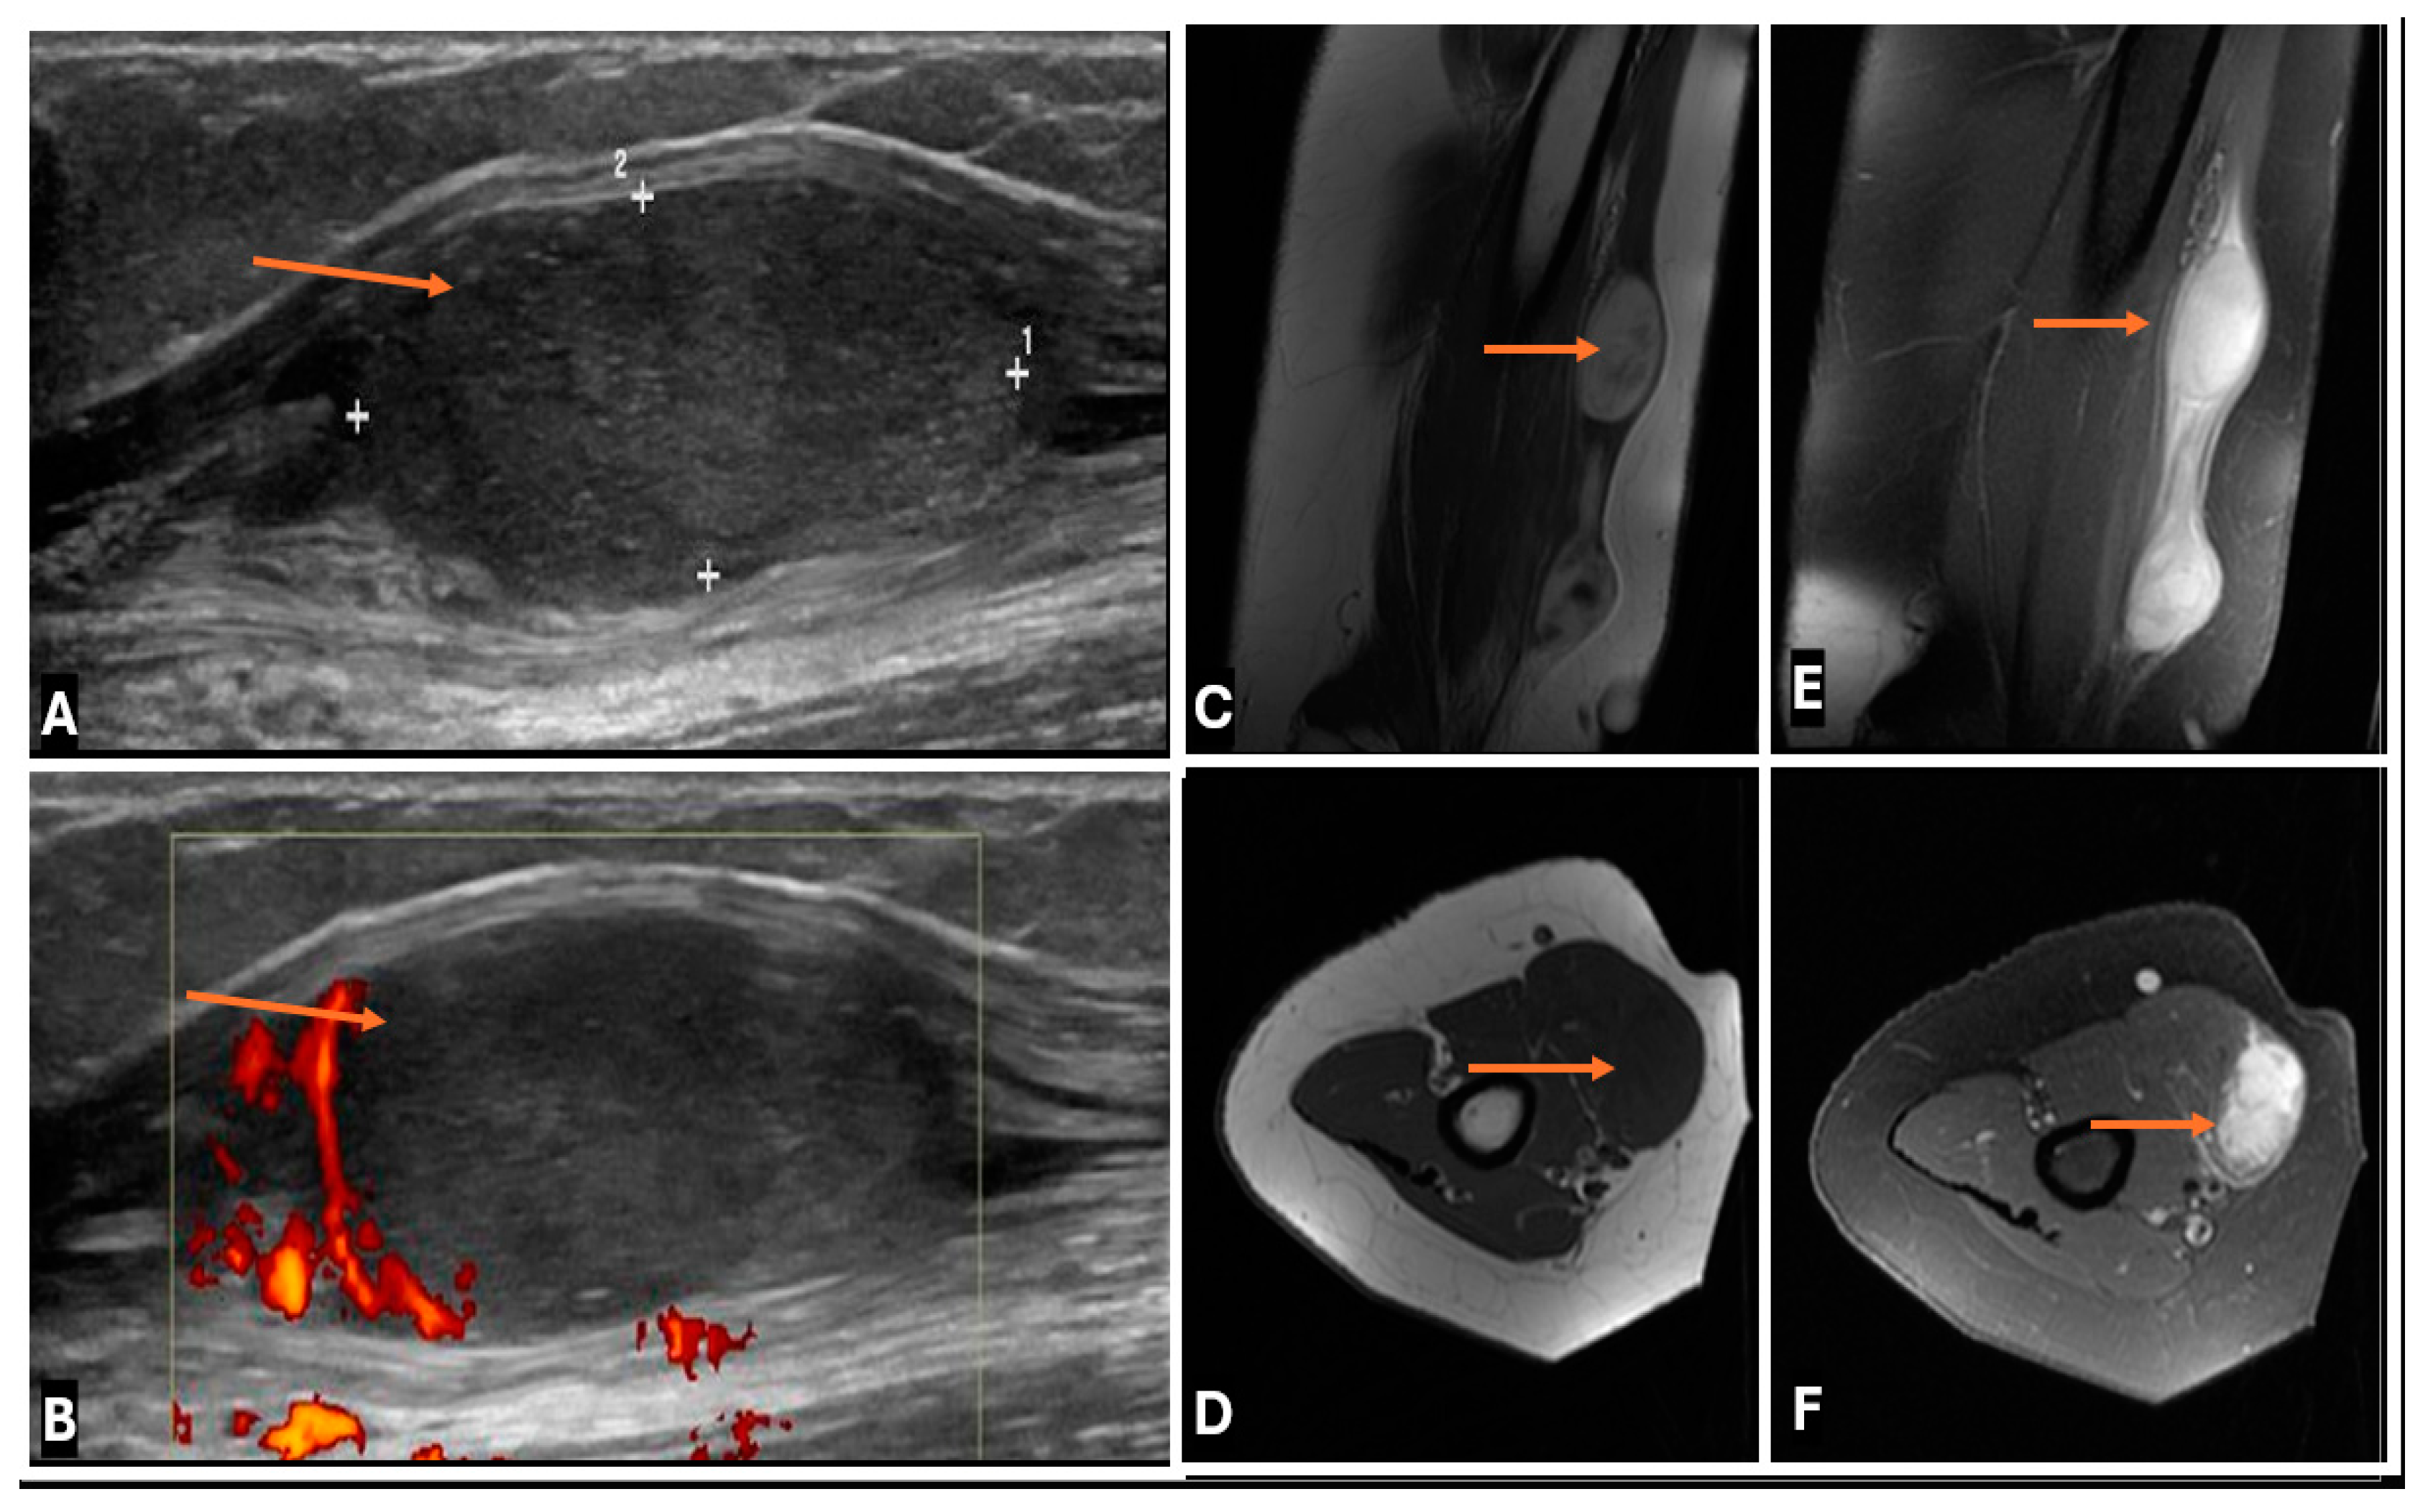

- Primary Sarcomas: Soft-tissue sarcomas are uncommon, accounting for just over 1% of adult malignancies. Synovial sarcoma, clear cell sarcoma, and epithelioid sarcomas are known to involve peripheral nerves. CT/MR reveals a large soft tissue mass with areas of necrosis or calcification and heterogeneous contrast enhancement. F-18 FDG uptake is useful for both tumor staging and treatment assessment (Figure 26, Figure 27 and Figure 28).